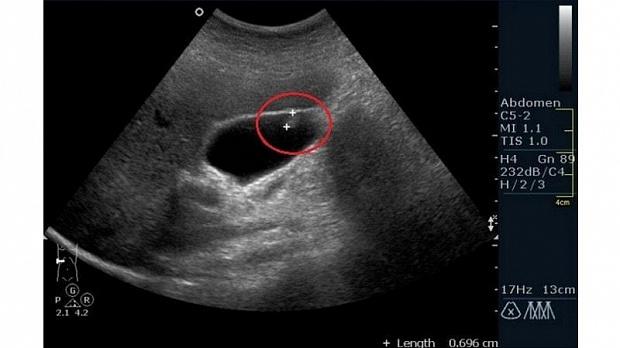

Обычно их находят случайно при ультразвуковом исследовании или после удаления желчного пузыря.

Чаще всего полипы - это безобидное разрастание слизистой оболочки или скопление холестерина. При ультразвуковом исследовании невозможно различить безобидный полип и рак.

Есть много разных методов диагностики. Ультразвуковое исследование позволяет очень хорошо рассмотреть желчный пузырь и полипы. Но полностью исключить вероятность рака ни один из методов диагностики не может.